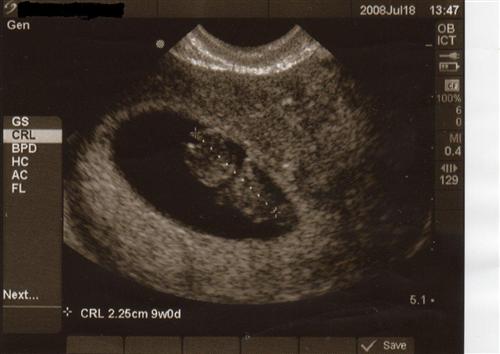

Baby's First Picture- July 18th, 2008- 9weeks, 6 days